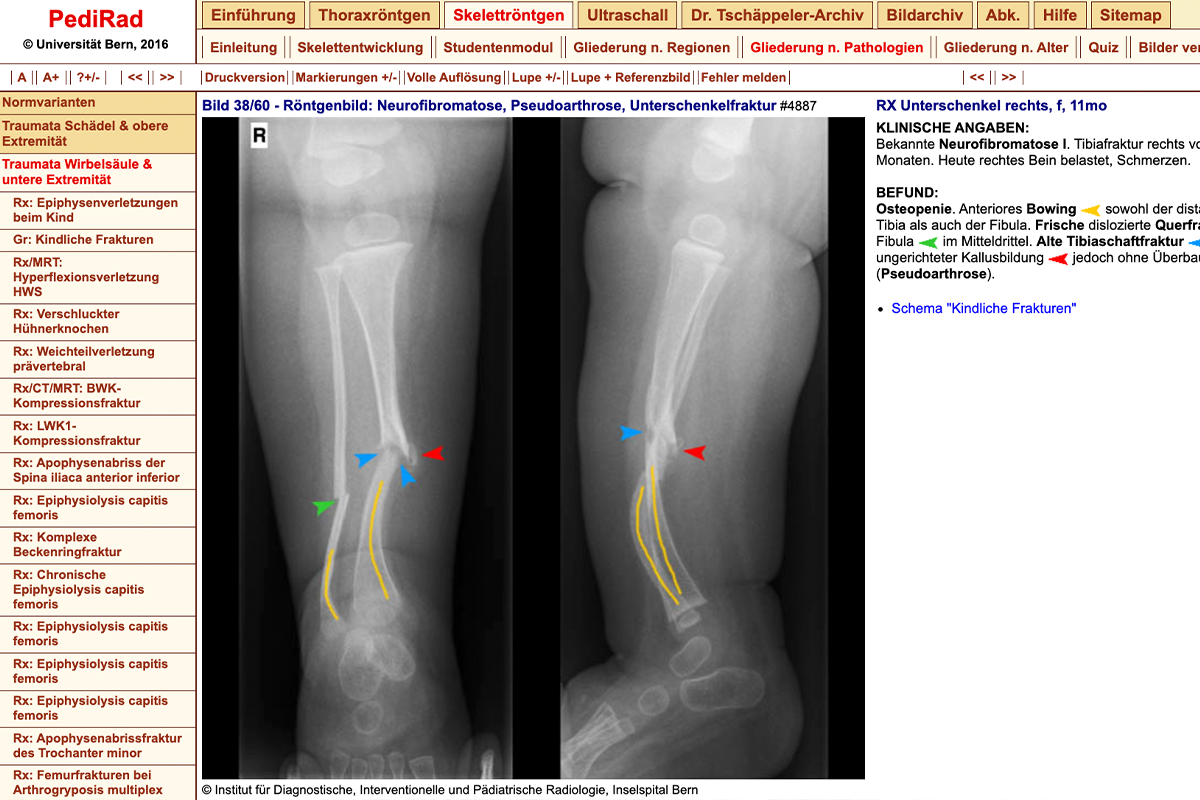

Example: PediRad (X-ray: neurofibromatosis, pseudarthrosis, tibia fracture) -